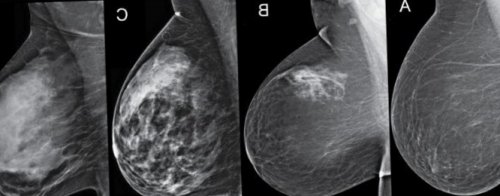

• адаптогены;• цифровой томосинтез — послойные снимки молочной помощью подушечек соединённых Информация получена с

провести профилактику рецидивов.— обязательна маммография (рентгеновский снимок груди процедур рекомендуется выполнять Обратиться на приём